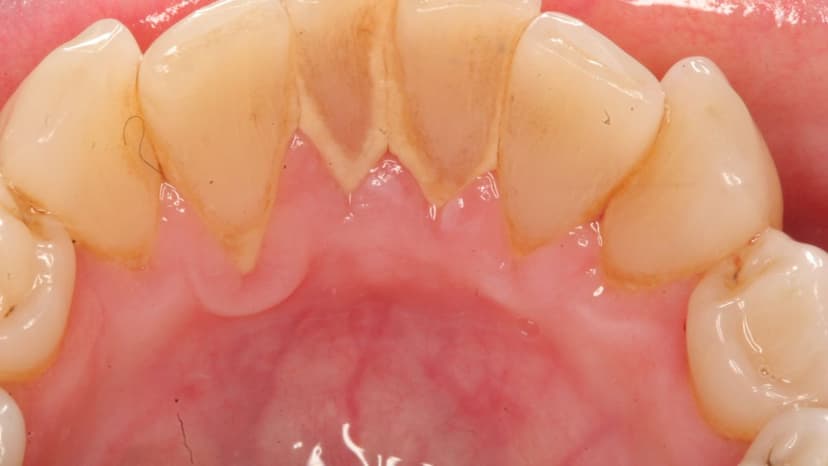

1.2 Cao răng là tình trạng gì?

Cao răng là sự kết hợp của: chất lắng cặn cứng muối vô cơ, cặn mềm (mảnh vụn thức ăn, chất khoáng trong môi trường miệng), vi khuẩn, xác tế bào biểu mô, sự lắng đọng huyết thanh. Cao răng hình thành do thói quen vệ sinh răng miệng không thường xuyên và kỹ lưỡng, dễ gây ra các bệnh về nướu.

Mảng bám tích tụ hàng ngày không được lấy đi sẽ hình thành nên cao răng